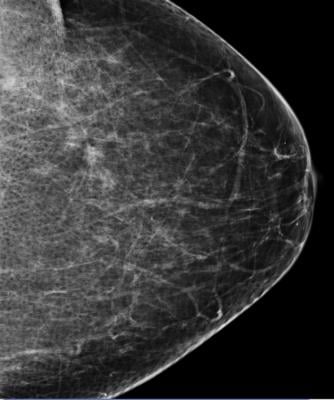

June 5, 2015 - Women aged 50-69 years who attend mammography screening reduce their risk of dying from breast cancer by 40 percent compared to women who are not screened, according to a major international review. The review covered the latest evidence on breast cancer screening.

Duffy continued: "Despite evidence that mammography screening is effective, we still need to carry out further research on alternative screening methods, such as the promising 'digital breast tomosynthesis'; a newly developed form of 3-D imaging which could potentially improve the accuracy of mammography in coping with more dense breast tissue.

The purpose of breast screening is to diagnose women with breast cancer earlier, therefore improving prognosis and reducing the number of late-stage cases and deaths. However, concerns have been raised over the negative impact of mammography screening - notably, false-positive results, overdiagnosis and possibly radiation-induced cancer. This new review builds upon previous evidence which suggests the potential benefits of breast screening outweigh the risks.